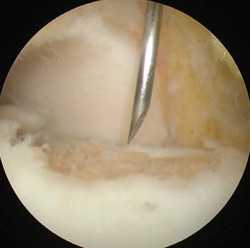

МРТ является ценным инструментом в комплексе диагностики ОХПТК для оценки отека костной ткани, а также выявления скрытых повреждений субхондральной кости и хрящевого покрытия, которые могут быть пропущены при стандартных рентгенограммах или даже КТ. МРТ – самый лучший инструмент оценки для определения стабильности и жизнеспособности фрагмента таранной кости при его отслоении и эта информация может быть решающей в тактике выбора того или иного метода хирургического лечения. Однако, для определения размеров отслоившегося фрагмента таранной кости наилучший метод КТ, так как данные размеров по МРТ могут не соответствовать действительности в сторону переоценки последних. Hepple с соавторами изучив многочисленные данные МРТ диагностики разработали систему классификации ОХПТК на основе этого метода (Табл. 2) [23]. Однако, наиболее широко принятая система классификации, основанная на КТ-это классификация Ferkel и Sgalione (Табл. 3; Рисунок 4) [24]. Классифицировать ОХПТК также возможно выполнить интраоперационно, на основе артроскопических данных о состоянии остеохондрального поражения. Наиболее широко используется система Ferkel/Cheng (Табл. 4) [25], эта система классификации, в отличие от обычных рентгенограмм, КТ и МРТ, лучше всего взаимосвязана с исходами лечения пациентов.

Благодаря современному оснащению нашей клиники сегодня мы можем отказаться от травматичных открытых операций на голеностопном суставе. На замену им пришла артроскопия.

Суть вмешательства проста. Через небольшие разрезы врач вводит в полость сустава специальную трубку, снабженную видеокамерой. Камера дает необходимый обзор, позволяя с высокой точностью проводить операцию. В ходе артроскопии медик либо удаляет некротизированный кусок костной ткани, чтобы он не доставлял человеку неудобств, либо, если некроз не окончательно поразил участок кости, крепит доставляющую неудобства часть к основному массиву с помощью специальных скобок или винтов.

Артроскопия, метод выбора для пациентов с рассекающим остеохондритом. Операция менее травматична, восстановление после нее проходит легче и быстрее.

В большинстве первичных случаях весь необходимый объем вмешательства может быть выполнен артроскопически.

Методика заключается в удалении всех отколовшихся фрагментов хряща и подлежащей некротизированной (умершей) кости. Если в кости под хрящом имеются кисты, они вскрываются и специальным образом обрабатываются. Затем особым интструментом выполняется микро перфорация кости. Это приводит к высвобождению факторов роста, которые заполняют дефект хряща таранной кости.

Операция выполняется под общей или спинальной анестезией. Выполняется стандартная артроскопическая ревизия голеностопного сустава, оцениваются размеры и локализация дефекта. Идеальным кандидатом на мозаичную остеохондропластику является пациент с дефектом хряща таранной кости диаметром более 10 мм. Важным является сохранение целостности остальных участков суставных поверхностей большеберцовой и таранной костей.

В ходе операции производят освежевание с помощью острого бора основания дефекта хряща таранной кости до появления кровоточащей поверхности